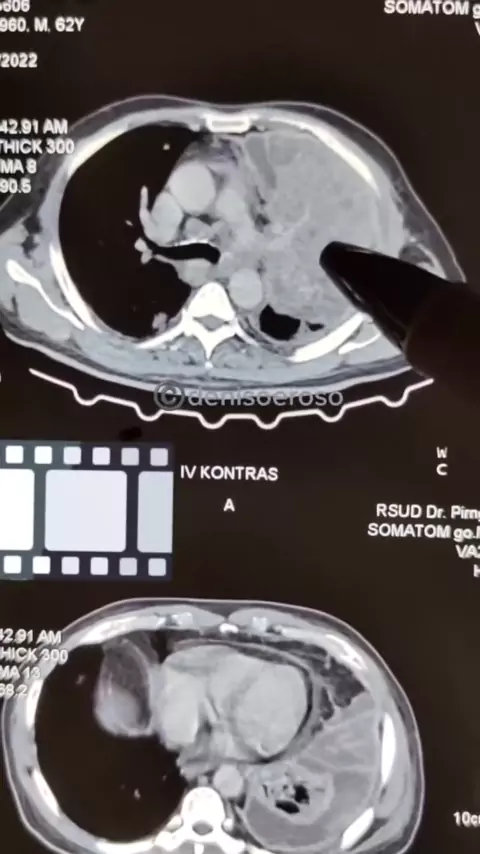

Kalau ada gambaran putih di paru harus hati-hati, penyakit paling sering terjadi gambaran putih di paru ialah effusi pleura (cairan di paru) atau kanker paru#SerunyaBelajarBareng#SerunyaBareng#infokesehatan#effusipleura#pleuraleffusion#kankerparu#lungcancer#tumorparu#onkologi#onkologiparu#dokterparu#spesialisparu#dokterviral#゚#